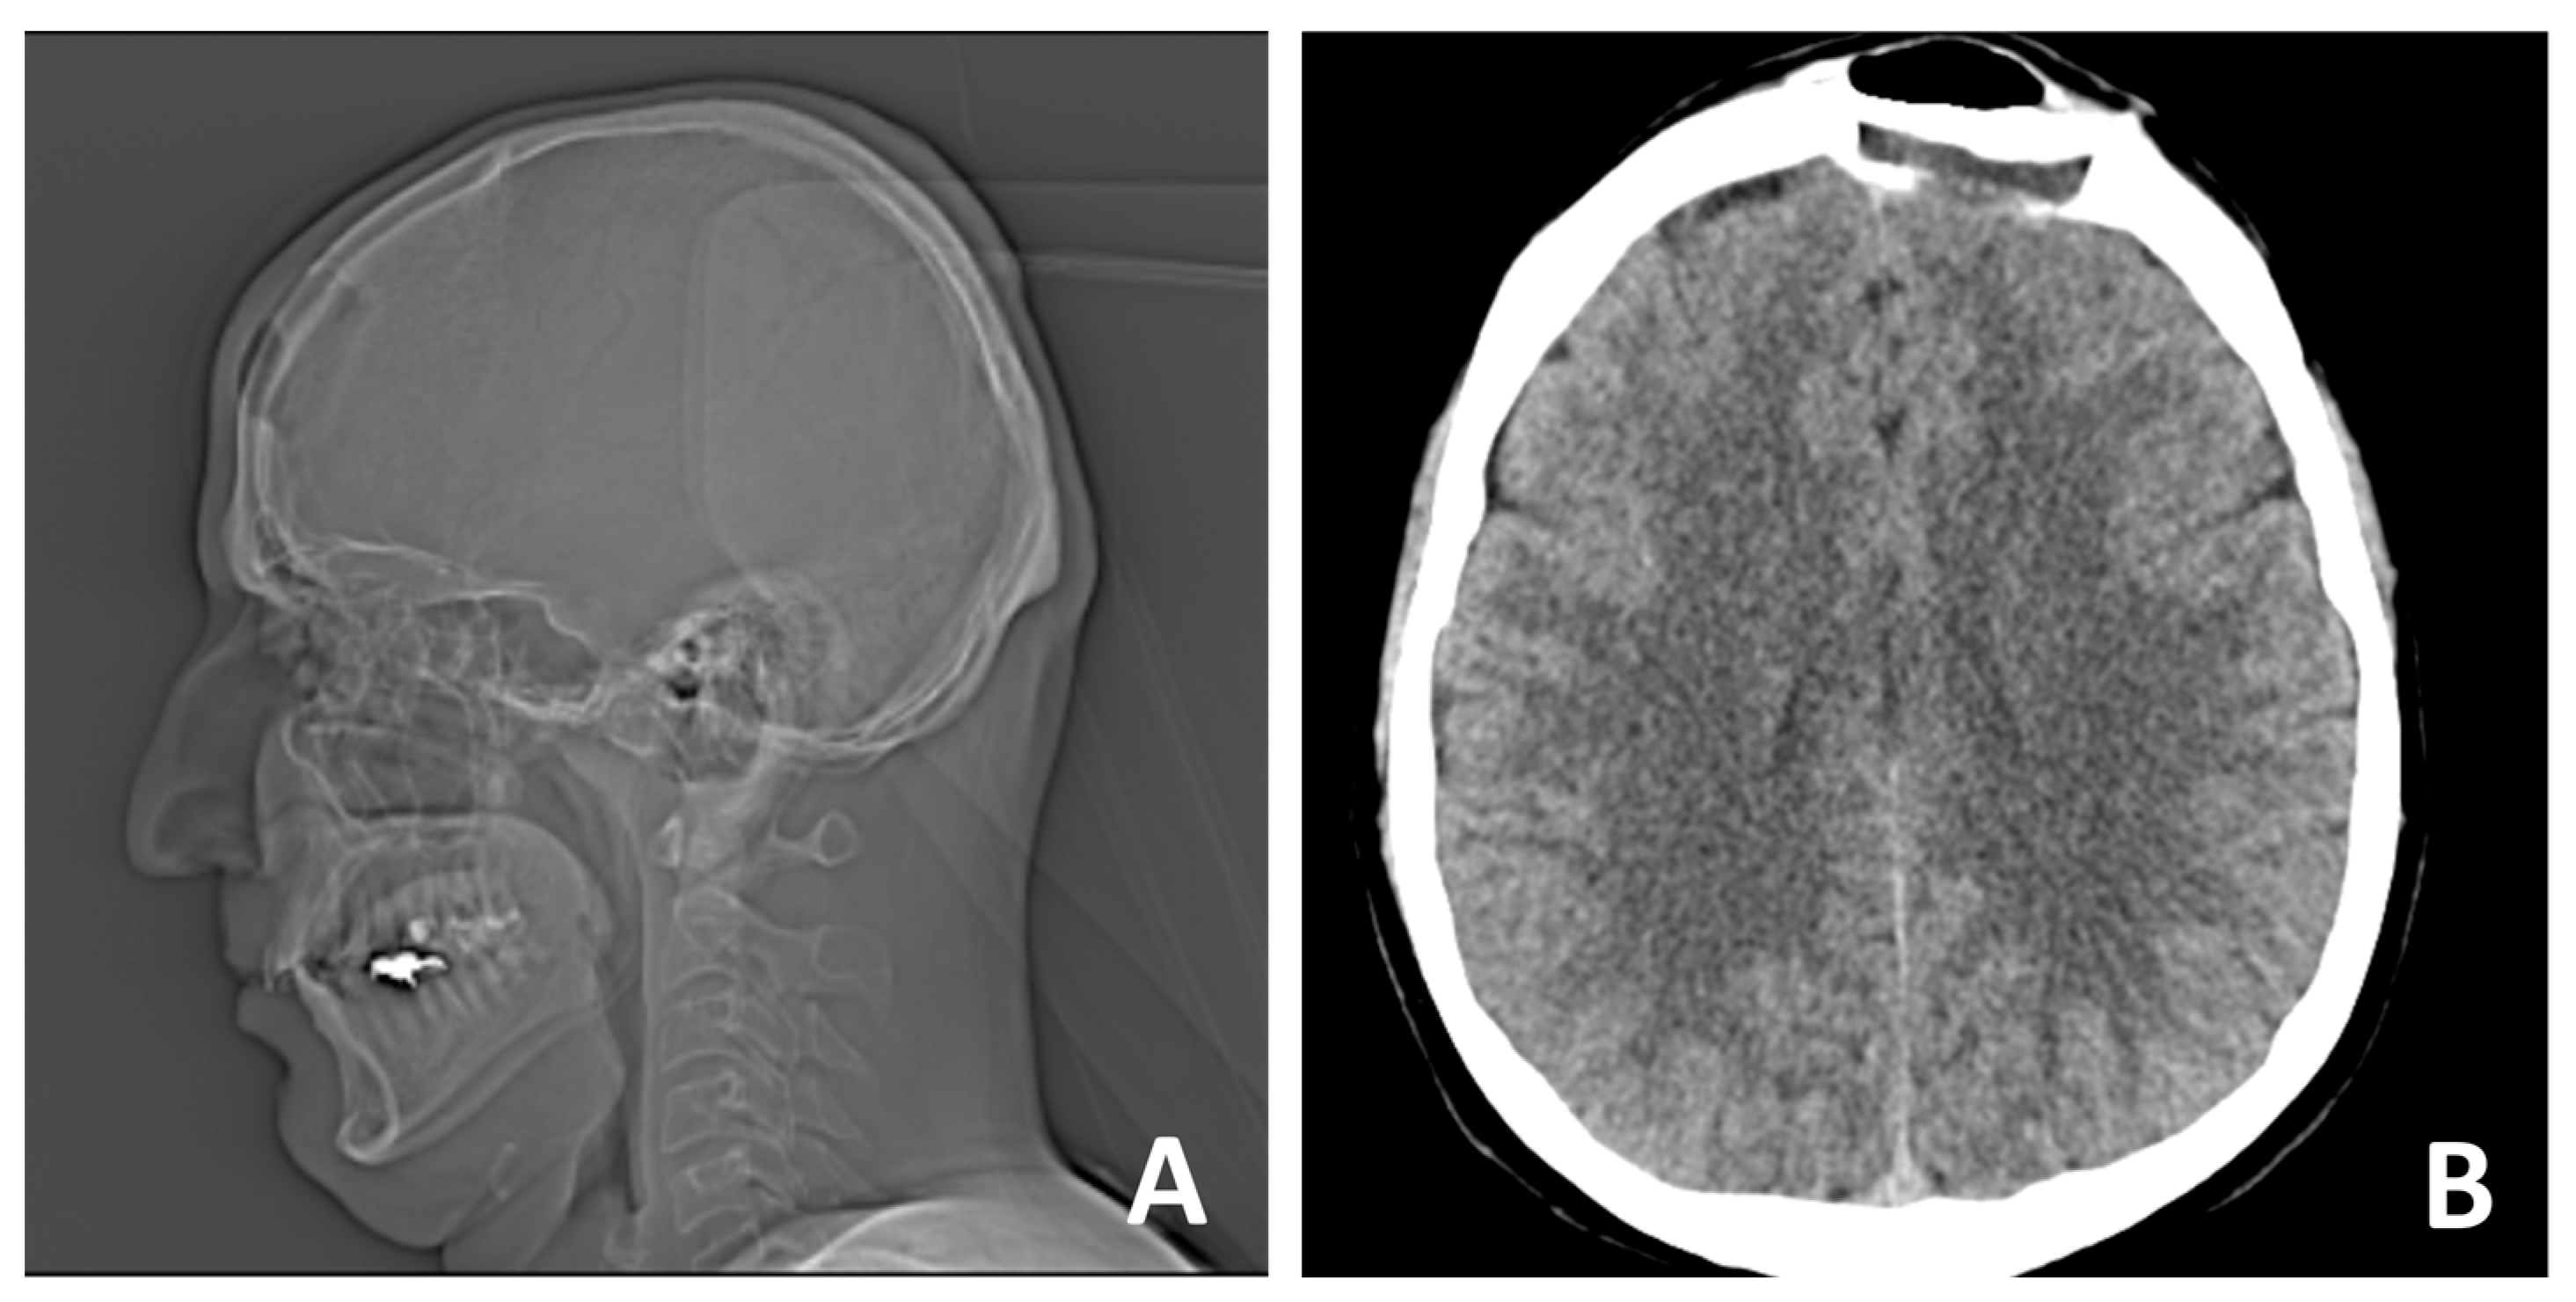

X-ray and CT scan performed prior to surgery revealed the presence of a well-defined bone lesion located in the left frontal bone. The lesion involves the diploic space, demonstrating a homogeneous internal structure and a characteristic spiculated anterior contour. This radiographic feature is associated with a sunburst or radiating trabecular pattern, commonly seen in vascular bone lesions. Additionally, the lesion is accompanied by localized expansion of the surrounding bone, without evidence of cortical destruction or soft tissue invasion. The dimensions of the lesion are approximately 27 mm in length and 16 mm in width. Based on the imaging characteristics—including its location, internal architecture, and expansion pattern—the findings are highly suggestive of a calvarial hemangioma. Further surgical and histopathological evaluation was indicated to confirm the diagnosis and guide treatment (Figure 1).

Figure 1. (A) X-ray and (B,C) CT scan prior to surgery reveal a bone lesion in the left frontal bone, involving the diploe, with a homogeneous structure, spiculated anterior contour, and local bone expansion.